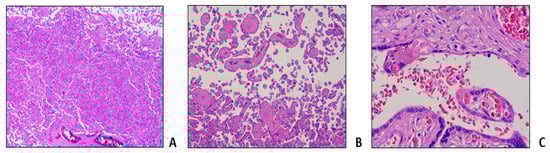

- Malinowski, A.K.; Dziegielewski, C.; Keating, S.; Parks, T.; Kingdom, J.; Shehata, N.; Rizov, E.; D’Souza, R. Placental histopathology in sickle cell disease: A descriptive and hypothesis-generating study. Placenta 2020, 95, 9–17. [Google Scholar] [CrossRef] [PubMed]